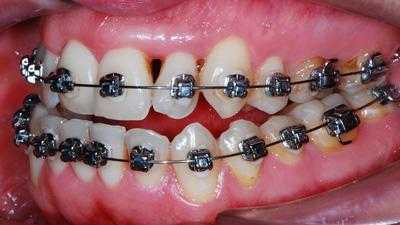

Установка брекетов

Во время основного этапа коррекции неправильного прикуса производят установку брекетов, для их фиксации используются клеевые композиты. Однако, в зависимости от типа брекетов используются разные методики установки. Каждый вестибулярный брекет наклеивают на переднюю поверхность зубов, которые нуждаются в коррекции, далее на них крепят опорные кольца, а в замочки продевают силовую дугу. Дуга изготавливается из материалов, обладающих эластичностью и упругостью, за счет чего она стремиться занять ту форму, которую ей придали первоначально.

С подросткового возраста, при постоянном прикусе выравнивание зубов и исправление патологий возможно только на несъемной аппаратуре — брекетах или съемных элайнерах. Для лечения дистальной окклюзии подходят все виды брекетов: внешние металлические и керамические, внутренние (лингвальные)

Часто дистальный прикус сопровождается смещением головки височно-нижнечелюстного сустава. Такие пациенты дополнительно используют суставную шину для коррекции движения и положения челюстей.